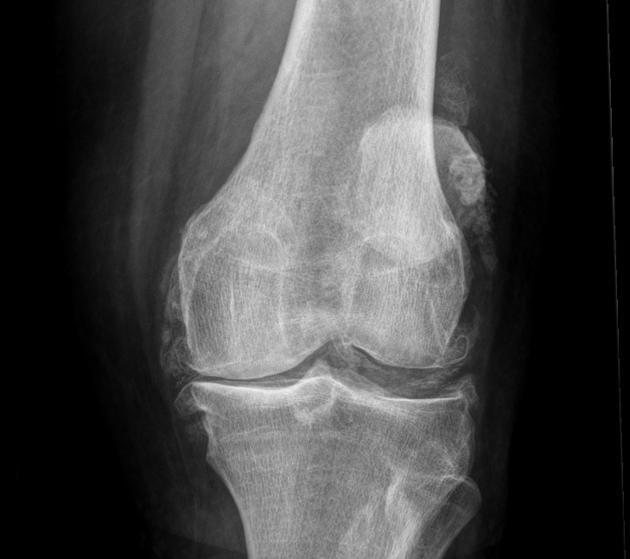

1/.膝関節:高齢者のしゃがむ&立っている困難で、多くの原因は、膝の変性、関節炎、滑膜炎、靭帯だけでなく、半月板の損傷によって引き起こされる。膝関節の変性では、冷たさの一定の年数の初期に現れ、階段を上る二重膝の弱さ、歩行が柔らかく再生され、後に現れた痛み、膨張、しゃがむ難しさの症状では、膝の脛骨プラットフォームであるため、顆間骨棘とギャップが広く、不均一に狭く、骨水腫、無菌性骨膜(滑膜炎)、半月板の摩耗や断裂、大腿四頭筋などの筋肉の緊張、靭帯損傷など。診断と鑑別は、血液検査、リウマチ4項目、抗環状シトルリン化ペプチド抗体検査、核磁気検査などで確認する。

紛れもなく、多くの中高年が障害を負う主な原因は変形性膝関節症であり、人工膝関節置換術の約85%を占めている。

関節の軟骨がすり減る程度が少なければ、患者は何も感じないが、軟骨のすり減りが深刻になるにつれて、すり減る範囲がどんどん大きくなり、すり減る厚みがどんどん大きくなり、関節が屈曲、伸展、活動する過程で、骨と骨の間の圧力が大きくなり、私たちの体は、骨と骨の間の関節にかかる圧力をよりよく軽減するために骨棘が現れ始め、骨が肥大化する。比較的小さな時間の誕生は、任意の症状を生成しませんが、より多くの大規模な、より多くの場合、患者の関節の機能に影響を与え、その結果、患者がしゃがむしゃがむしゃがむダウンすることはできませんしたい、脚を曲げたい正常な位置に曲げることはできません、一部の患者はまた、高齢者の上記の状況は非常に一般的である、我々は障害物をまっすぐ表示されます呼び出す変形性関節症は、65歳以上の50%に見られる。。

- X線検査の主な目的は、関節腔が著しく狭くなっているかどうかを判断することである。狭くなっている主な理由は、軟骨がかなり薄くなり、自然な関節空間が狭くなっているからです。また、高齢者の関節はレントゲンでよく判断できます。骨の形成が多いかどうか(骨棘)それが体のどの部分に特異的に形成されるのか、高齢者ではどのような機能に影響を及ぼすのか、また、高齢者ではどのような機能が低下するのか。オステオイドの形成と関節腔の狭小化は、変形性関節症における最も典型的な変化である。。